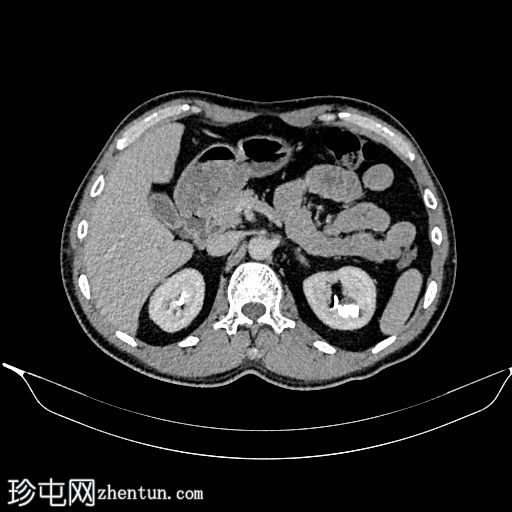

CT

轴位

平扫

双期增强

冠状位

左肾极间区钙化,形成一个相对下垂的平面,周围有非下垂的液体(乳状钙)。增强扫描显示该区域被造影剂充盈。

乳状钙是肾盏憩室的典型表现,本例亦是如此。